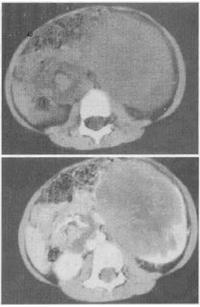

- 单项选择题 患儿,男,3岁。腹部包块伴反复发热1个月余。CT扫描见图。最有可能的诊断是()。

D、肾母细胞瘤

- D